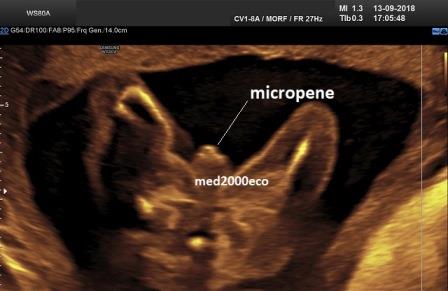

Diagnosi ecografica prenatale

La diagnosi ecografica prenatale è solo di sospetto. Le caratteristiche ecografiche prenatali possono essere caratterizzate da: